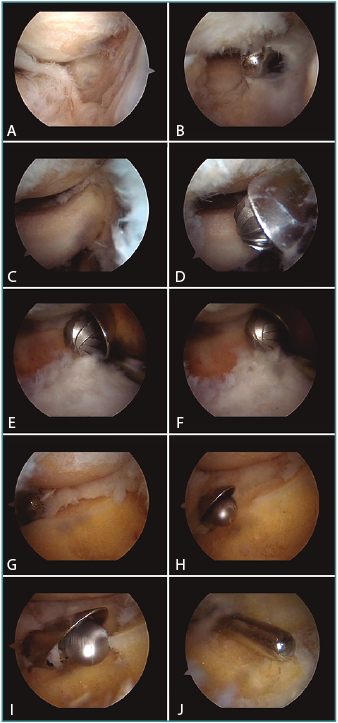

El procedimiento se inicia realizando una artroscopia exploradora básica del codo, donde se definan los portales anteromedial (AM) (o medial proximal) y portales anterolateral (AL) y mediolateral directo (MLD) de instrumentación. Se comienza con una evaluación del compartimento anterior. La mayoría de los procesos degenerativos del codo, bien sea de origen postraumático o reumatoide, asociarán sinovitis, osteofitos, cuerpos libres, contracturas capsulares, además de defectos de cartílago en la superficie de la cabeza radial y el capitellum (Figura 1A). Suele ser necesaria la realización de una sinovectomía anterior (Figura 1B) y la resección de cuerpos libres si están presentes, con cuidado para no lesionar la cápsula articular.

A continuación y tras obtener una visión clara de la cabeza del radio desde el portal AM (Figura 1C), se procede a la resección de la cabeza radial. Esta se inicia por los tres cuartos anteriores, que se resecan con una fresa motorizada cilíndrica introducida a través del portal AL (Figura 1D-F). La resección debe incluir el espesor completo del cartílago articular y el espesor de la cabeza del radio hasta aproximadamente 2-3 mm del cuello del radio. El cirujano puede ayudarse de movimientos suaves de pronosupinación del codo para permitir un acceso más preciso y completo de la fresa a la cabeza a resecar (Figura 1E-F). El cuarto posterior restante de la cabeza se reseca con la lente en el portal AM pero con ayuda del portal MLD. A través de dicho portal, se pueden introducir sinoviotomos y fresas de menor tamaño que permiten completar la resección (Figura 1G-J). En total, la resección tiene un espesor de aproximadamente 0,8-1 cm. Debe respetarse el ligamento anular para evitar causar una inestabilidad radiocubital proximal.

Figura 1. Técnica de la capitectomía artroscópica. Se comienza con una evaluación del compartimento anterior desde un portal anteromedial de visión (A). Suele ser necesaria la realización de una sinovectomía anterior (B), lo que permite obtener una visión clara de la cabeza del radio (C); se procede a la resección de la cabeza radial. Esta se inicia por los tres cuartos anteriores, que se resecan con una fresa motorizada cilíndrica introducida a través del portal anterolateral (D-F). El cuarto posterior restante de la cabeza se reseca desde el portal mediolateral directo (G-J).